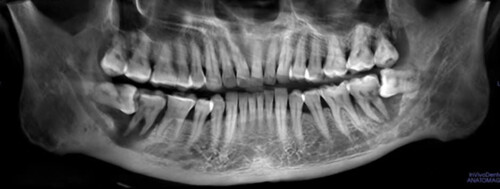

Răng khôn (răng số tám hay răng hàm lớn thứ ba) là răng mọc cuối cùng, thường mọc ở độ tuổi trưởng thành từ 18 đến 25 tuổi. Đây là răng hay gây nhiều biến chứng nhất trên cung hàm. Trong quá trình mọc và suốt thời gian tồn tại, răng khôn gây ra rất nhiều tai biến.

Răng khôn (răng số tám hay răng hàm lớn thứ ba) là răng mọc cuối cùng, thường mọc ở độ tuổi trưởng thành từ 18 đến 25 tuổi. Đây là răng hay gây nhiều biến chứng nhất trên cung hàm. Trong quá trình mọc và suốt thời gian tồn tại, răng khôn gây ra rất nhiều tai biến. Các tai biến do răng khôn gây ra cần phải điều trị chiếm một tỷ lệ cao trong các bệnh về răng miệng, bao gồm: